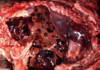

Describe the area of necrosis?

massive hepatocellular necrosis